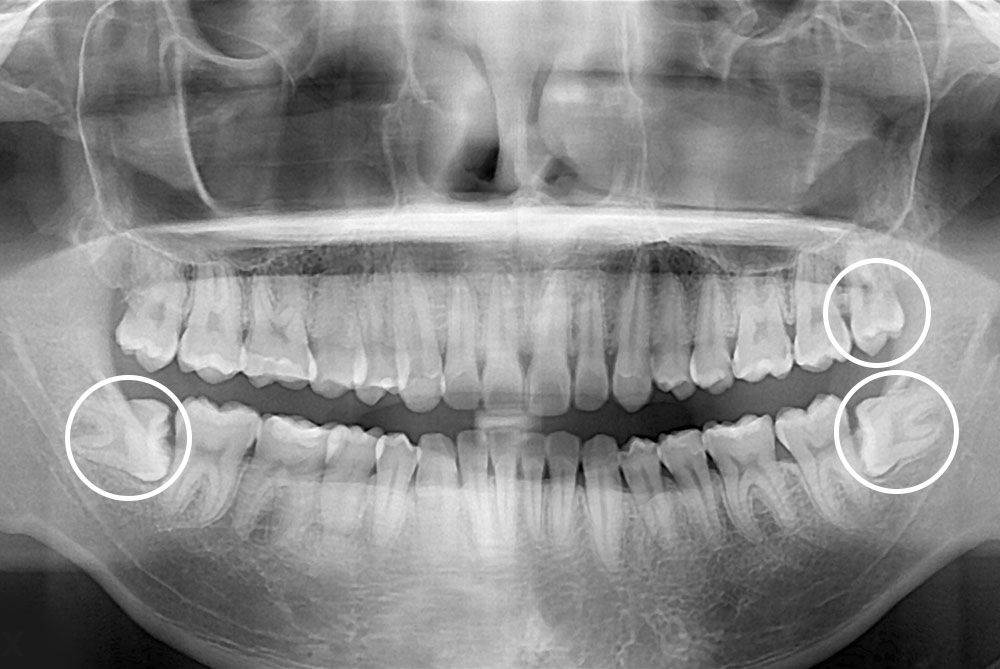

[사랑니] 매복 사랑니 발치

치료전 : 2019-07-30